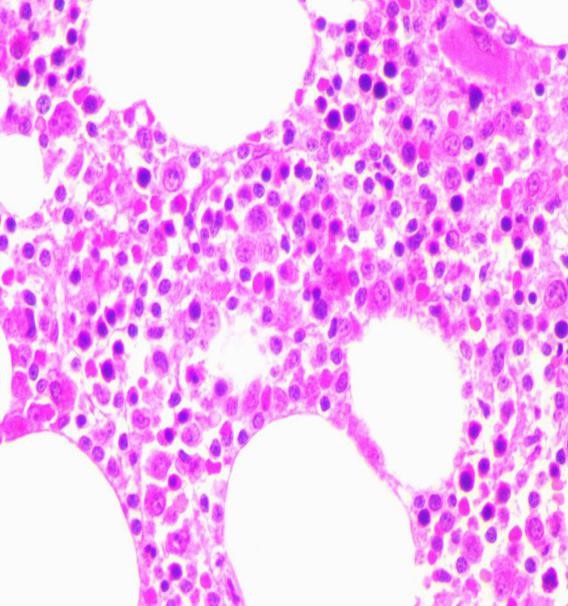

骨髓活检病理:造血细胞间可见异型淋巴细胞浸润,散在或结节状分布,部分呈窦内分布,胞体小至中等大小,核圆或轻度不规则,染色质致密;网染(1+)。

免疫组化染色结果:CD42b(巨核+)、CD79a(+)、CD3(-)、MPO(粒+)、CD20(+)、CD34(-)、CD5(-)、CD43(+)、Bcl-2(+)、Bcl-6(-)、GLUT-1(红+)、CD4(-)、CD8(-)、TIA-1(-),提示B细胞淋巴瘤累犯骨髓(见图5)。

图5